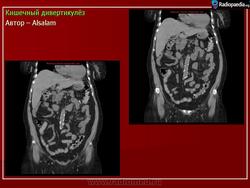

Кишечный дивертикулёз. Пнд, 09/09/2013 - 22:01 #1 Катенёв Валенти... Не на сайте Был на сайте: 7 лет 5 месяцев назад Зарегистрирован: 22.03.2008 - 22:15 Публикации: 54876 Дивертикулёз сигмы и нисходящей ободочной кишки Fig.23.: Radiographic image: multiple, round filling defects are seen on the sigma and on the descending colon. Втр, 11/11/2014 - 13:06 #2 Катенёв Валенти... Не на сайте Был на сайте: 7 лет 5 месяцев назад Зарегистрирован: 22.03.2008 - 22:15 Публикации: 54876 Продолжение. Приложения:

Дивертикулёз сигмы и нисходящей ободочной кишки